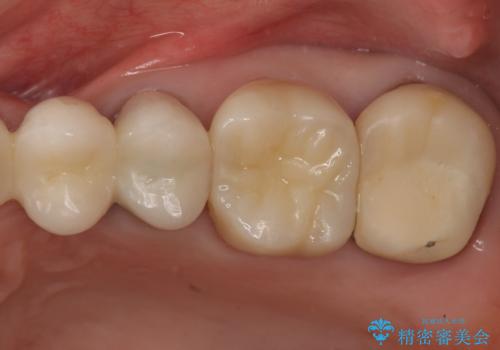

向かい合わせの歯の咬みこみが強くインレーよりも強度の高いクラウンでの治療となりました。その中でも色が白くある程度の薄さでも耐久性を発揮するフルジルコニアクラウンでの修復を行いました。適合も良く色調もとてもなじんだため大変喜んでいただけました。